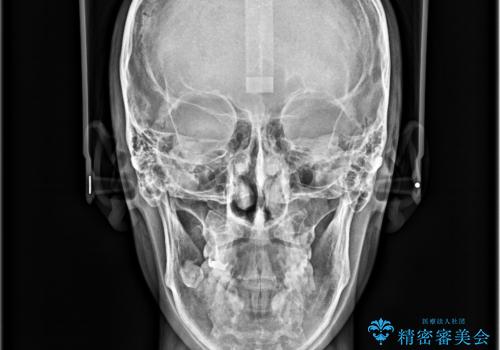

ガタガタの歯並び、八重歯をなおしたい、骨格性下顎前突 カモフラージュ矯正

骨格的に上顎骨が小さいために相対的に下顎骨が前に出ていたため、歯の傾きなど理想的な仕上がりが難しく、外科矯正ではなく歯列矯正の場合はカモフラージュ矯正になること説明の上、矯正治療を進めることになりました。

患者様にはかなり満足していただける結果となりました。